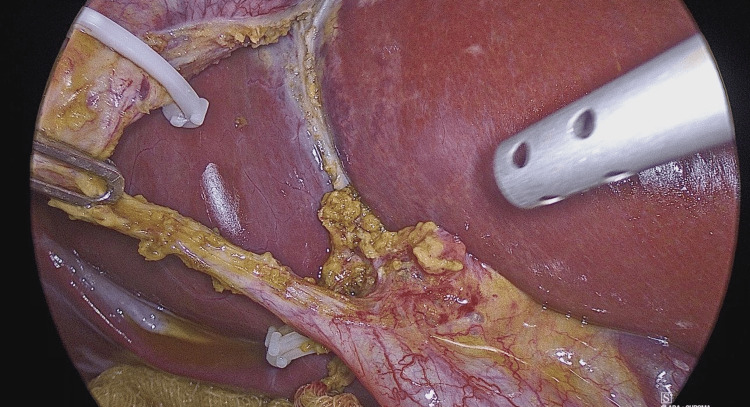

The standard LC procedure is typically initiated by creating a large posterior window (extended critical view of safety) to clearly identify the cystic duct and artery while ensuring that liver structures are excluded (Figure 1). Once Calot’s triangle is identified, OTC is performed to clarify the biliary anatomy, identify any filling defects, and avoid unnecessary intervention in the biliary tree. This involves making a horizontal incision on the cystic duct to introduce the OTC catheter.

In a smaller subset of cases (seven cases, 33%), OTC and flushing of the CBD were sufficient to remove microlithiasis. However, in most cases (14 cases, 67%), the SpyGlass Discover system was utilized (Figures 2–3). The SpyGlass Discover catheter, which is 65 cm long, allows for direct visual exploration of the CBD. Among these cases, nine (43%) involved small stones that were pushed into the duodenum using pressure washing, while the remaining five cases (24%) required basket removal (Video 1), mechanical lithotripsy, or laser fragmentation for larger stones (Video 2).

After stone removal, transcystic OTC was performed to confirm that the CBD was fully cleared and that there was no bile leakage. Finally, the cystic duct was sealed with a clip, and the cholecystectomy was completed. All videos and figures were taken from our original work in the general surgery department.